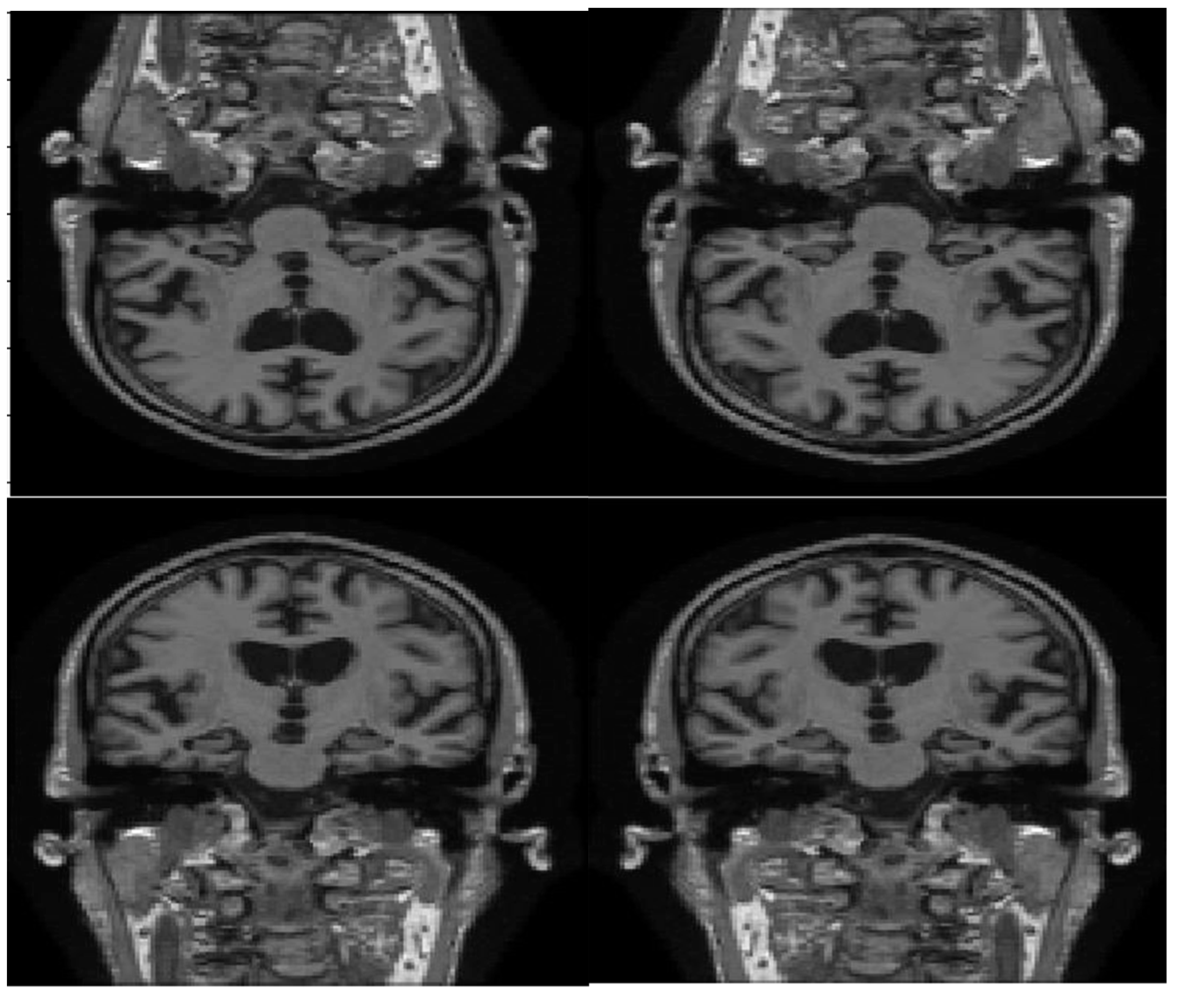

3.2. Image Fusing and Preprocessing

4.3.1. Image Fusion Performance